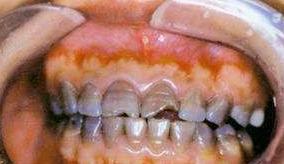

三、全口牙的内源性着色。

*四环素牙:在牙发育矿化期,服用的四环素族药物,可被结合到牙组织内,使牙着色。也可导致牙釉质发育不全从而导致牙齿变色。(四环素在牙本质内,因结合部位的深浅而使牙本质着色的程度有所不同,当着色带越靠近釉牙本质界时,越易着色,因而在婴儿早期形成外层牙本质时,用药影响最大。)

*氟斑牙:氟主要损害牙釉质发育期牙胚的造釉细胞,因此,过多的氟只有在牙发育矿化期进入机体,才能发生氟牙症(六七岁之前,避免儿童在高氟地区)

临床上常按其轻、中、重度而分为白垩型(轻度)、变色型(中度)和缺损型(重度)三种类型。

注:饮用水中氟含量过高产生氟斑牙,过低则形成龋齿,当饮水含氟量为1ppm时,既有防龋作用,又不致形成氟斑牙。因此牙膏可选含氟牙膏,有助于预防蛀牙,但对于吞咽控制能力还不完善的儿童,误吞含氟牙膏就会增加氟的摄入量,而过量的氟则容易导致氟牙症,所以小朋友经量少用或者不用含氟牙膏,可定期去牙科涂氟保护牙齿。